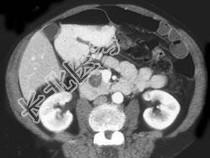

- 单项选择题患者,女, 57岁,上腹部隐痛半年余, CT片,最可能的诊断是 ( )

A、胰腺癌

B、胰腺脓肿

C、胰腺假性囊肿

D、胰腺囊腺瘤

E、胰岛细胞瘤